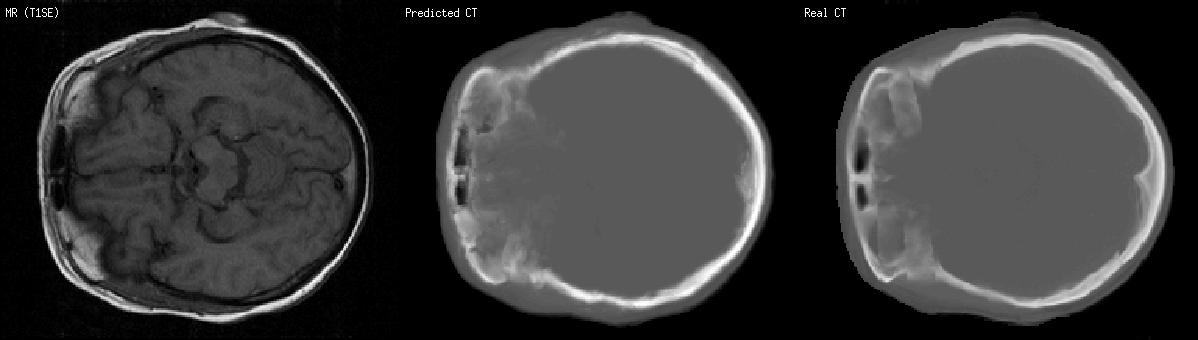

Example : a MR scan slice of a human brain, its predicted CT scan slice computed based on a training set of other MR and CT scans, and the real CT scan (i.e. the ground truth in order to see if predictions are good):

The two black holes in all images stand for cavities (so, air) in the forehead. White in the CT images stand for the skull. In the MR image, they all look black, so one cannot distinguish bone from air in MR scans just from the pixel intensity. Image patches and location are considered, in order to bring more information.